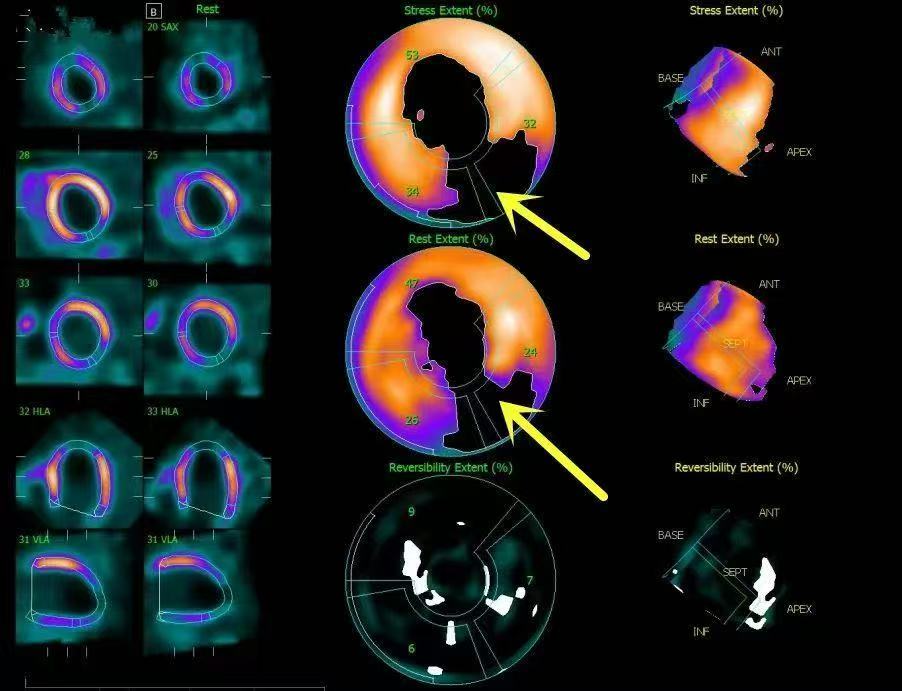

(图释:在心脏ECT检查图像上,那些能摄取一定量放射性示踪剂的心肌会在图像中呈亮块,如果有心肌缺血,图像就会偏暗,缺血越严重颜色越暗。)